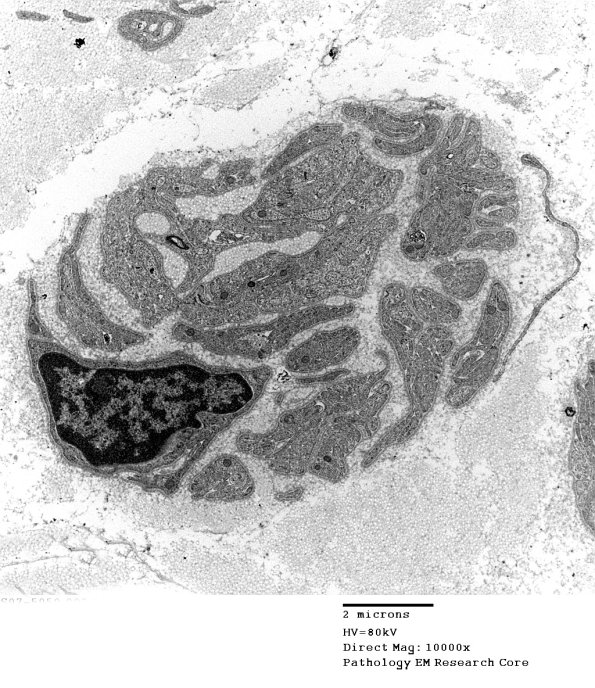

8D2,3 The residual endoneurial structures are largely bands of Büngner. (electron micrographs)